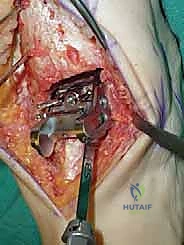

الخطوات الجراحية التفصيلية لاستبدال مفصل الكاحل بتقنية STAR

تُعد هذه الجراحة من أروع وأدق الإجراءات في عالم جراحة العظام. يقوم الأستاذ الدكتور محمد هطيف وفريقه الطبي في صنعاء بتنفيذها وفق بروتوكول عالمي صارم لضمان نسب نجاح تقارب 100٪. فيما يلي تفصيل دقيق لخطوات العملية، مدعوماً بالصور من داخل غرفة العمليات.

4. وضع أدلة القطع (Jig Placement and Alignment)

تعتمد دقة الجراحة على المحاذاة الصحيحة. يتم استخدام أجهزة توجيه متطورة (Jigs) تثبت على عظمة الساق باستخدام دبابيس معدنية. يتم التحقق من صحة الزوايا والمحاور باستخدام جهاز الأشعة السينية المباشر داخل غرفة العمليات (C-arm Fluoroscopy). يضمن الدكتور هطيف أن يكون القطع موازياً للأرض تماماً عند وقوف المريض.

5. القطع العظمي الظنبوبي (Tibial Bone Cut)

باستخدام منشار جراحي دقيق التذبذب، يتم إزالة شريحة رقيقة جداً (بضعة مليمترات) من السطح السفلي التالف لعظمة الظنبوب. يتم القطع بحذر شديد لتجنب إصابة الأوتار الخلفية أو الأوعية الدموية.

6. القطع العظمي الكاحلي (Talar Bone Cut)